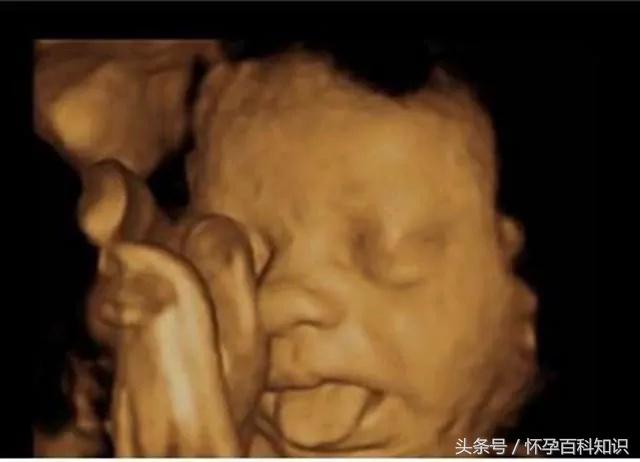

我要打个长长的哈欠。

菌菌告诉你,小家伙不仅会做各种动作,表情更是丰富的不得了。

我还会吐舌头、扮鬼脸!